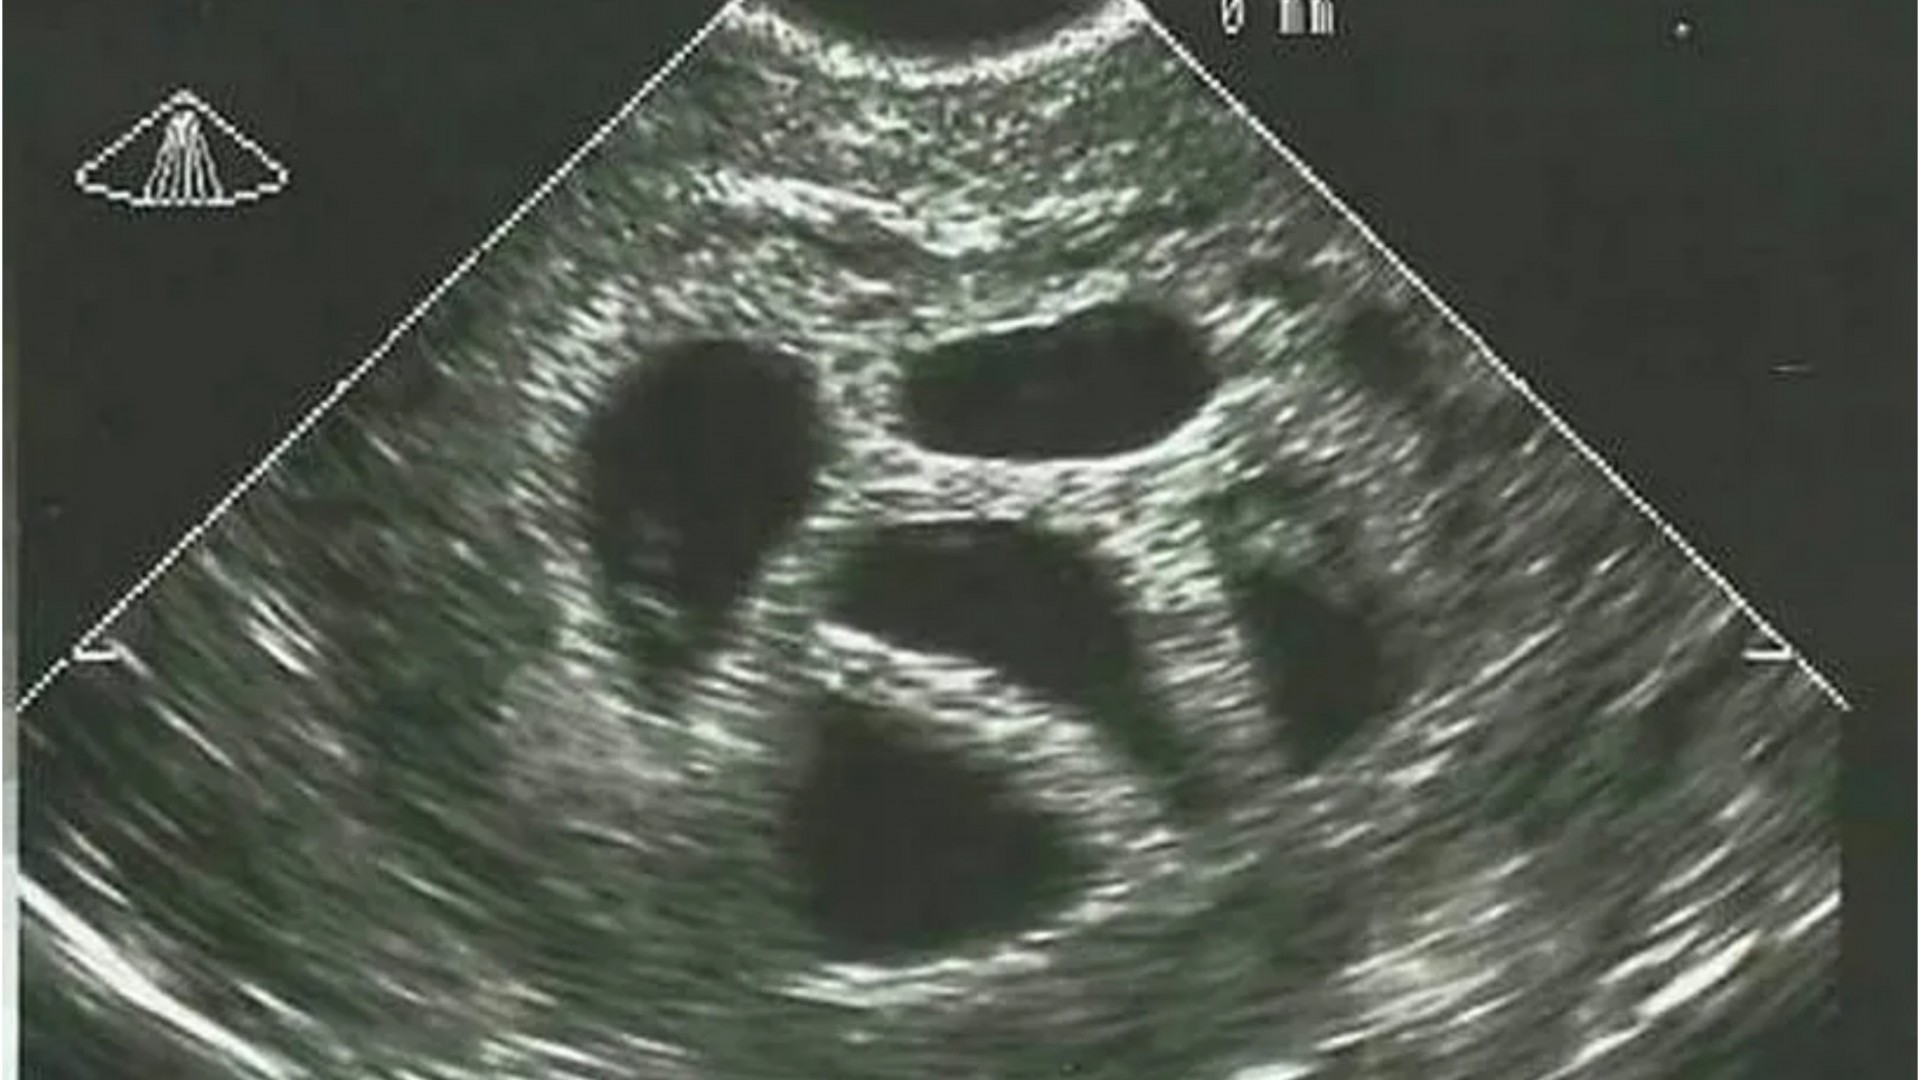

Доктор видел петорка на ултразвук, па ја советувал идната мајка да абортира: 20 години подоцна ја објави таа фотографија

Во свет каде што секоја одлука за животот се претвора во дебата, приказната за Американката Сузан Томпсон го враќа фокусот на она што е суштинско - верата, љубовта и храброста да...